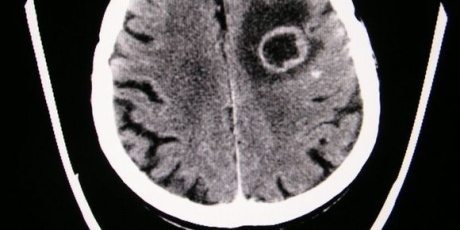

Nebezpečné bakteriální onemocnění není sice masově rozšířené, ale je velmi nebezpečné – snadným přenosem kapénkovou infekcí a někdy až fatálními komplikacemi a následky.

K nejohroženějším věkovým skupinám patří malé děti ve věku zhruba od jednoho do čtyř let a pak dospívající. Prvotními příznaky bývají teploty, podrážděnost, objevuje se bolest hlavy. „V další fázi je nápadná ochablost, spavost a konečně se objevují i kožní projevy a to už je rozvinutá forma a je potřeba urychleně vyhledat lékařskou pomoc, průběh onemocnění meningokokovou nákazou je velice rychlý,“ varuje MUDr. Josef Trmal.